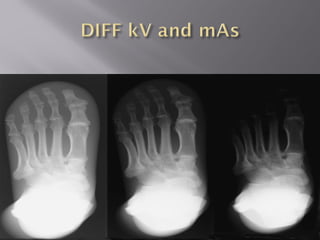

 Should be kept minimum to

 For faster cassette we have to compromise on

the kV and penetration but exposure time is

 Should bekept minimum to decrease/minimize motion unsharpness  For faster cassette we have to compromise on the kV and penetration but exposure time is minimized